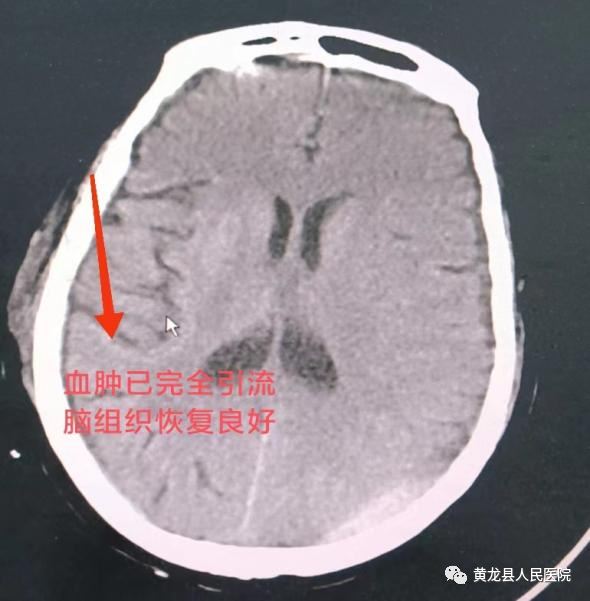

术前颅脑MRI 、术后颅脑CT

确定手术方案告知患者及家属,取得同意后,于近日,外科团队在杨磊副主任医师带领下,手麻科的协助、配合下,为患者顺利实施了右侧慢性硬膜下血肿钻孔引流术,手术非常成功,术后患者生命体征平稳,经过重症监护室精心治疗护理,目前患者已康复出院。

此项手术时间段、切口小,采用微创治疗,患者及家属非常满意,对外科及手麻科医务人员表示感谢。